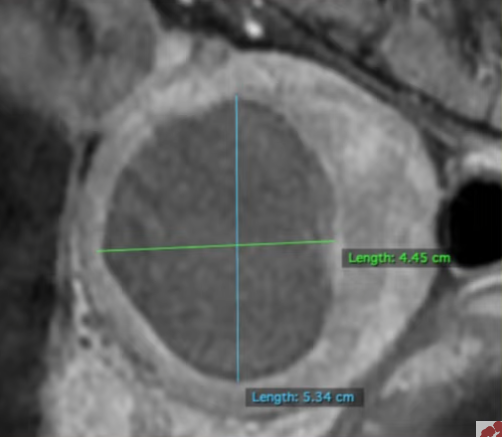

MRI